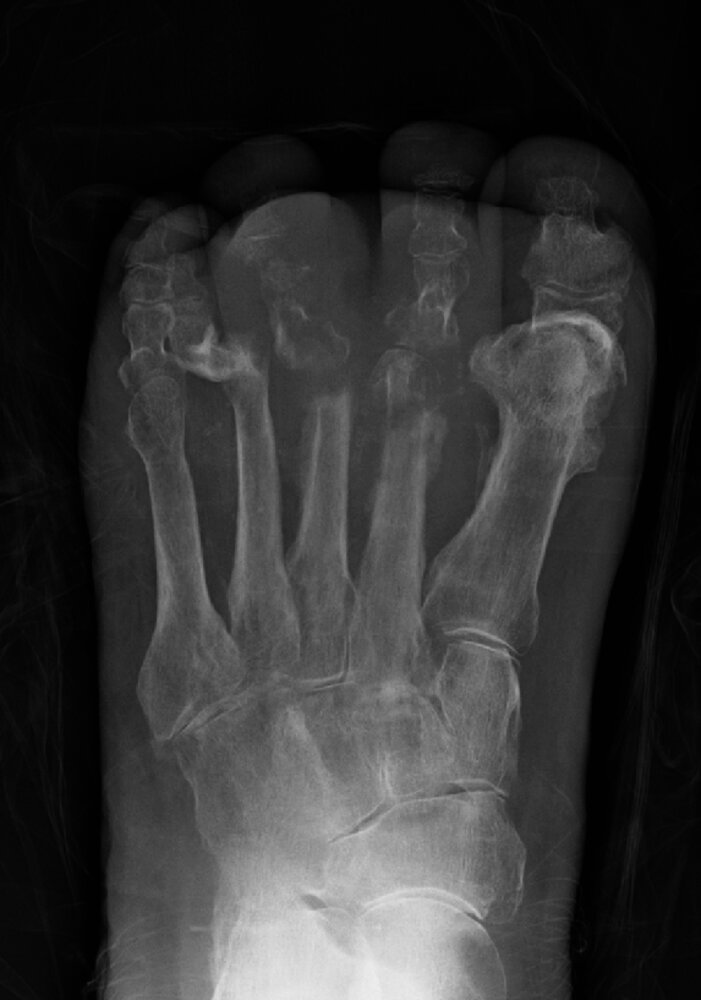

Diabetic neuropathic arthropathy (Charcot foot) [14]

• Neuropathic arthropathy is the development of bone destruction, subluxation/dislocation, and deformity secondary to neuropathy (most commonly diabetic neuropathy).

• The tarsus and tarsometatarsal joints are most commonly affected.

• Clinical presentation depends on the stage.

• Chronic stage: painless bony deformities, midfoot collapse (rocker-bottom foot deformity), osteolysis, fractures

• Diagnosis requires x-ray (first line) and MRI (in diagnostic uncertainty).

• Initial treatment is conservative (mechanical offloading, treatment of diabetes); surgery is used for severe or refractory cases.

Diabetic neuropathic arthropathy can be challenging to distinguish from diabetic foot osteomyelitis; in diagnostic uncertainty, consider bone biopsy. [3]